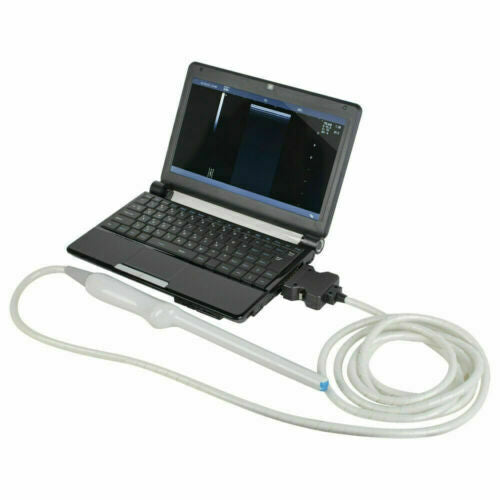

DIAGNOSTIC ULTRASOUND MACHINES FOR SALE

Laptop Ultrasound Machine Portable Medical Scanner with Transvaginal Probe USA 6945040100362

Sale price$ 1,798.00

Regular price$ 1,918.00